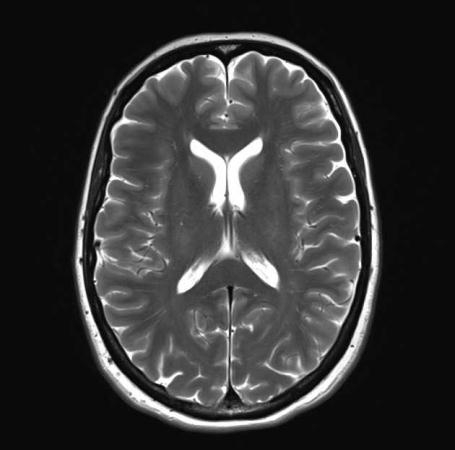

NoTumor

Fig - 1 : Flowchartofproposedmethod TheDatasetofbrainwithtumor: TheDatasetofbrainwithouttumor: